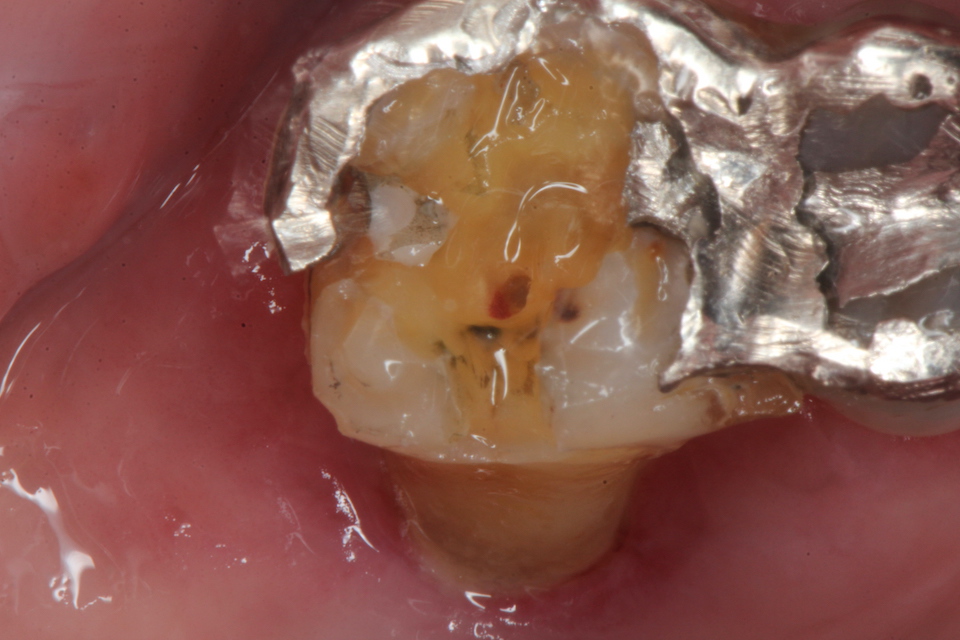

ということで、歯髄は死にかけているな。。と思って天蓋を除去してみた。

天蓋を穿通した。少し出血している。死にかかっている歯に麻酔は要らない。麻酔とは健全な痛みを感じる歯を削る時に必要なだけだ。麻酔が必要な歯を削るということは僕に言わせれば、過剰診療と言っても良い。

上顎6の根管は3つあるはずだ。探している

口蓋根の出血は少ない。ほとんど失活している